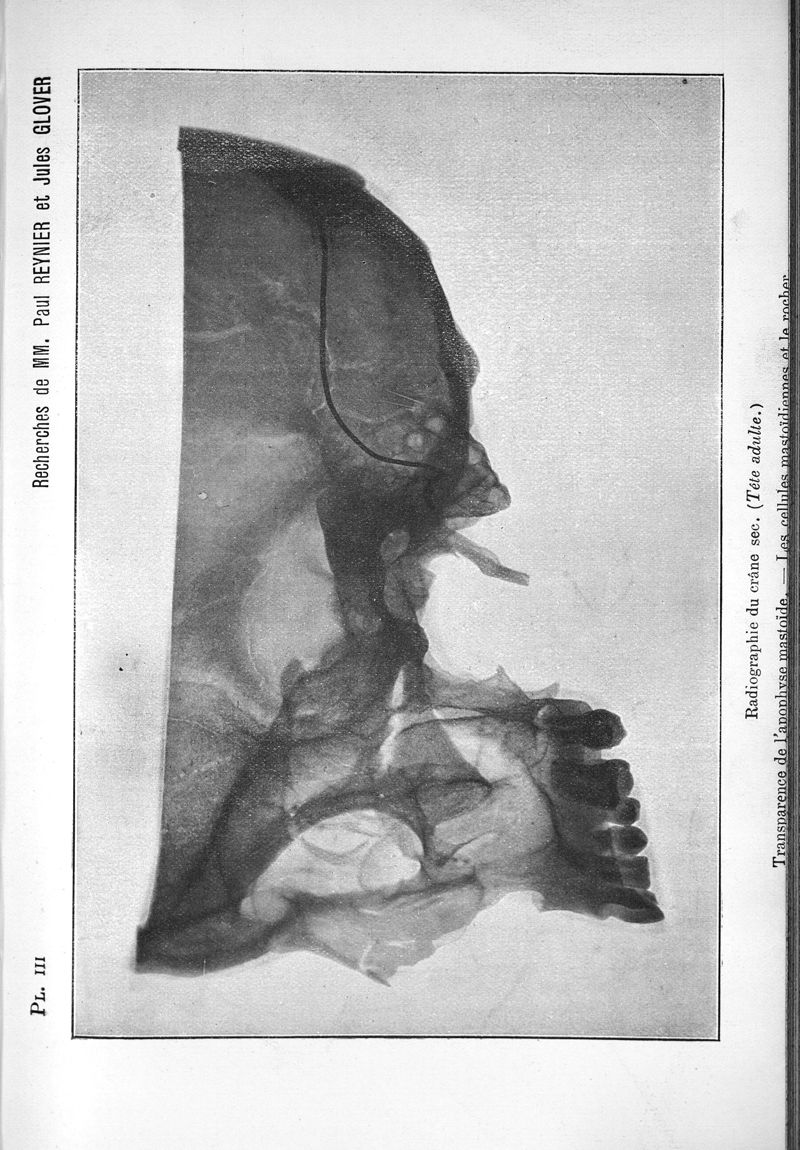

Archives internationales de laryngologie, d'otologie et de rhinologie

tome 10, 1897. - Paris : Maloine, 1897.